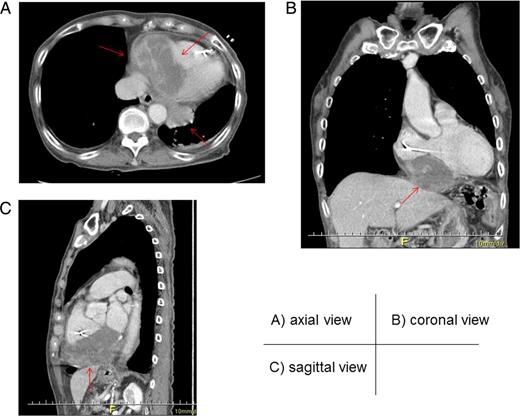

Axial (A), coronal (B) and sagittal (C) views of enhanced computed tomography. A tumor (arrow) measuring 90.0 × 56.4 × 60.0 mm, with heterogenous low enhancement and an unclear border invaded into the inferior myocardium.

No specific findings for PCL have been reported. Most of the tumors seem to appear as poor enhancement structures infiltrating adjacent chambers [7]. It often involves the right atrium and the conductive system, thus leading to many types of arrhythmias [8]. On the other hand, lymphoma tends not to invade large vessels because it is softer than the other malignant tumors [9]. Indeed, in our case, the right coronary artery penetrated the tumor without any signs of invasion, even though the tumor infiltrated the adjacent right chambers. This is the first case report that has described the CTCA findings of PCL. The observation of the coronary artery without invasion by the tumor may be a significant finding of PCL. Further accumulation of cases will be needed to determine whether such findings of CTCA are useful for the diagnosis of PCL.